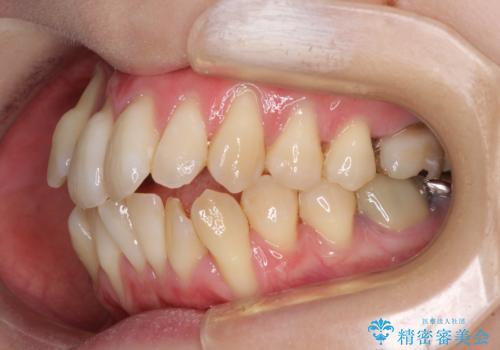

上顎骨よりも下顎骨の幅が広く、更には下顎骨が左側に変位していたため、より良い咬み合わせを達成することを目的として、急速拡大装置を用いて上顎骨を拡大することとしました。

歯根露出が顕著であったため、歯の移動は早く、スムーズに治療を終えられるかと思いましたが、歯槽骨が硬く、治療は長期間に及びました。

過剰に力をかけ続ける事態となり、一部の歯では変色したり、神経が失活したりとトラブルが続きました。

それでも当初とは比べものにならないほど、綺麗な歯列に仕上げることができました。